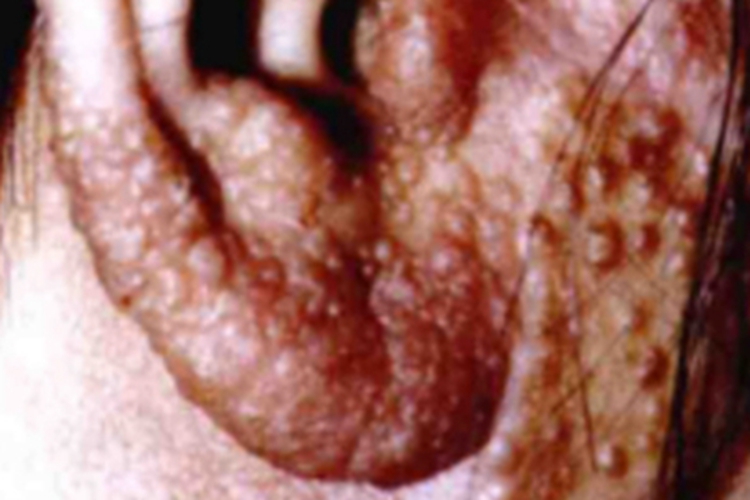

无绿藻病的皮损可累及耳部,局部出现米粒大小的丘疹、结节,数量较多,像很多小疙瘩,皮损会互相融合成片状,病情呈慢性进行性进展。